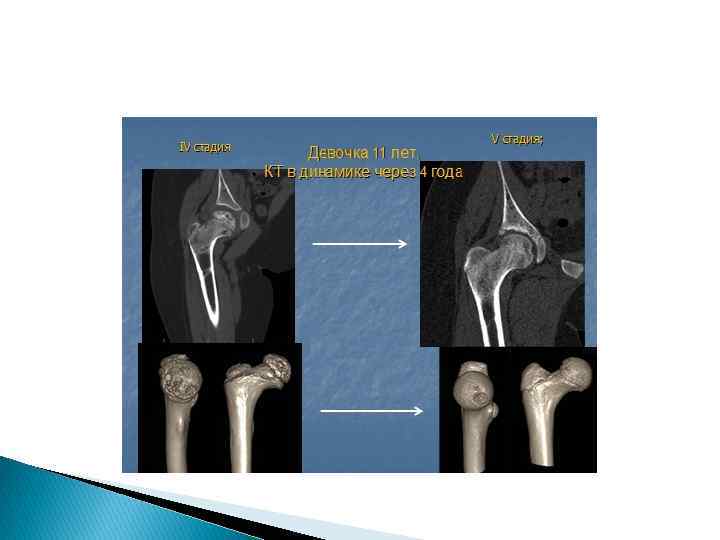

Остеохондропати я головки правого бедра. Поздняя, четвертая, стадия заболевания. Деталь рентгенограммы отчетливо показывает ряд кистевидных просветлений преимущественно в латеральной части головки бедренной кости

Остеохондропатия голсвки правого бедра у 23 -летнего мужчины. Пятая стадия заболевания. Грибовидная головка. Незначительные клинические объективные и субъективные" отклонения от нормы.